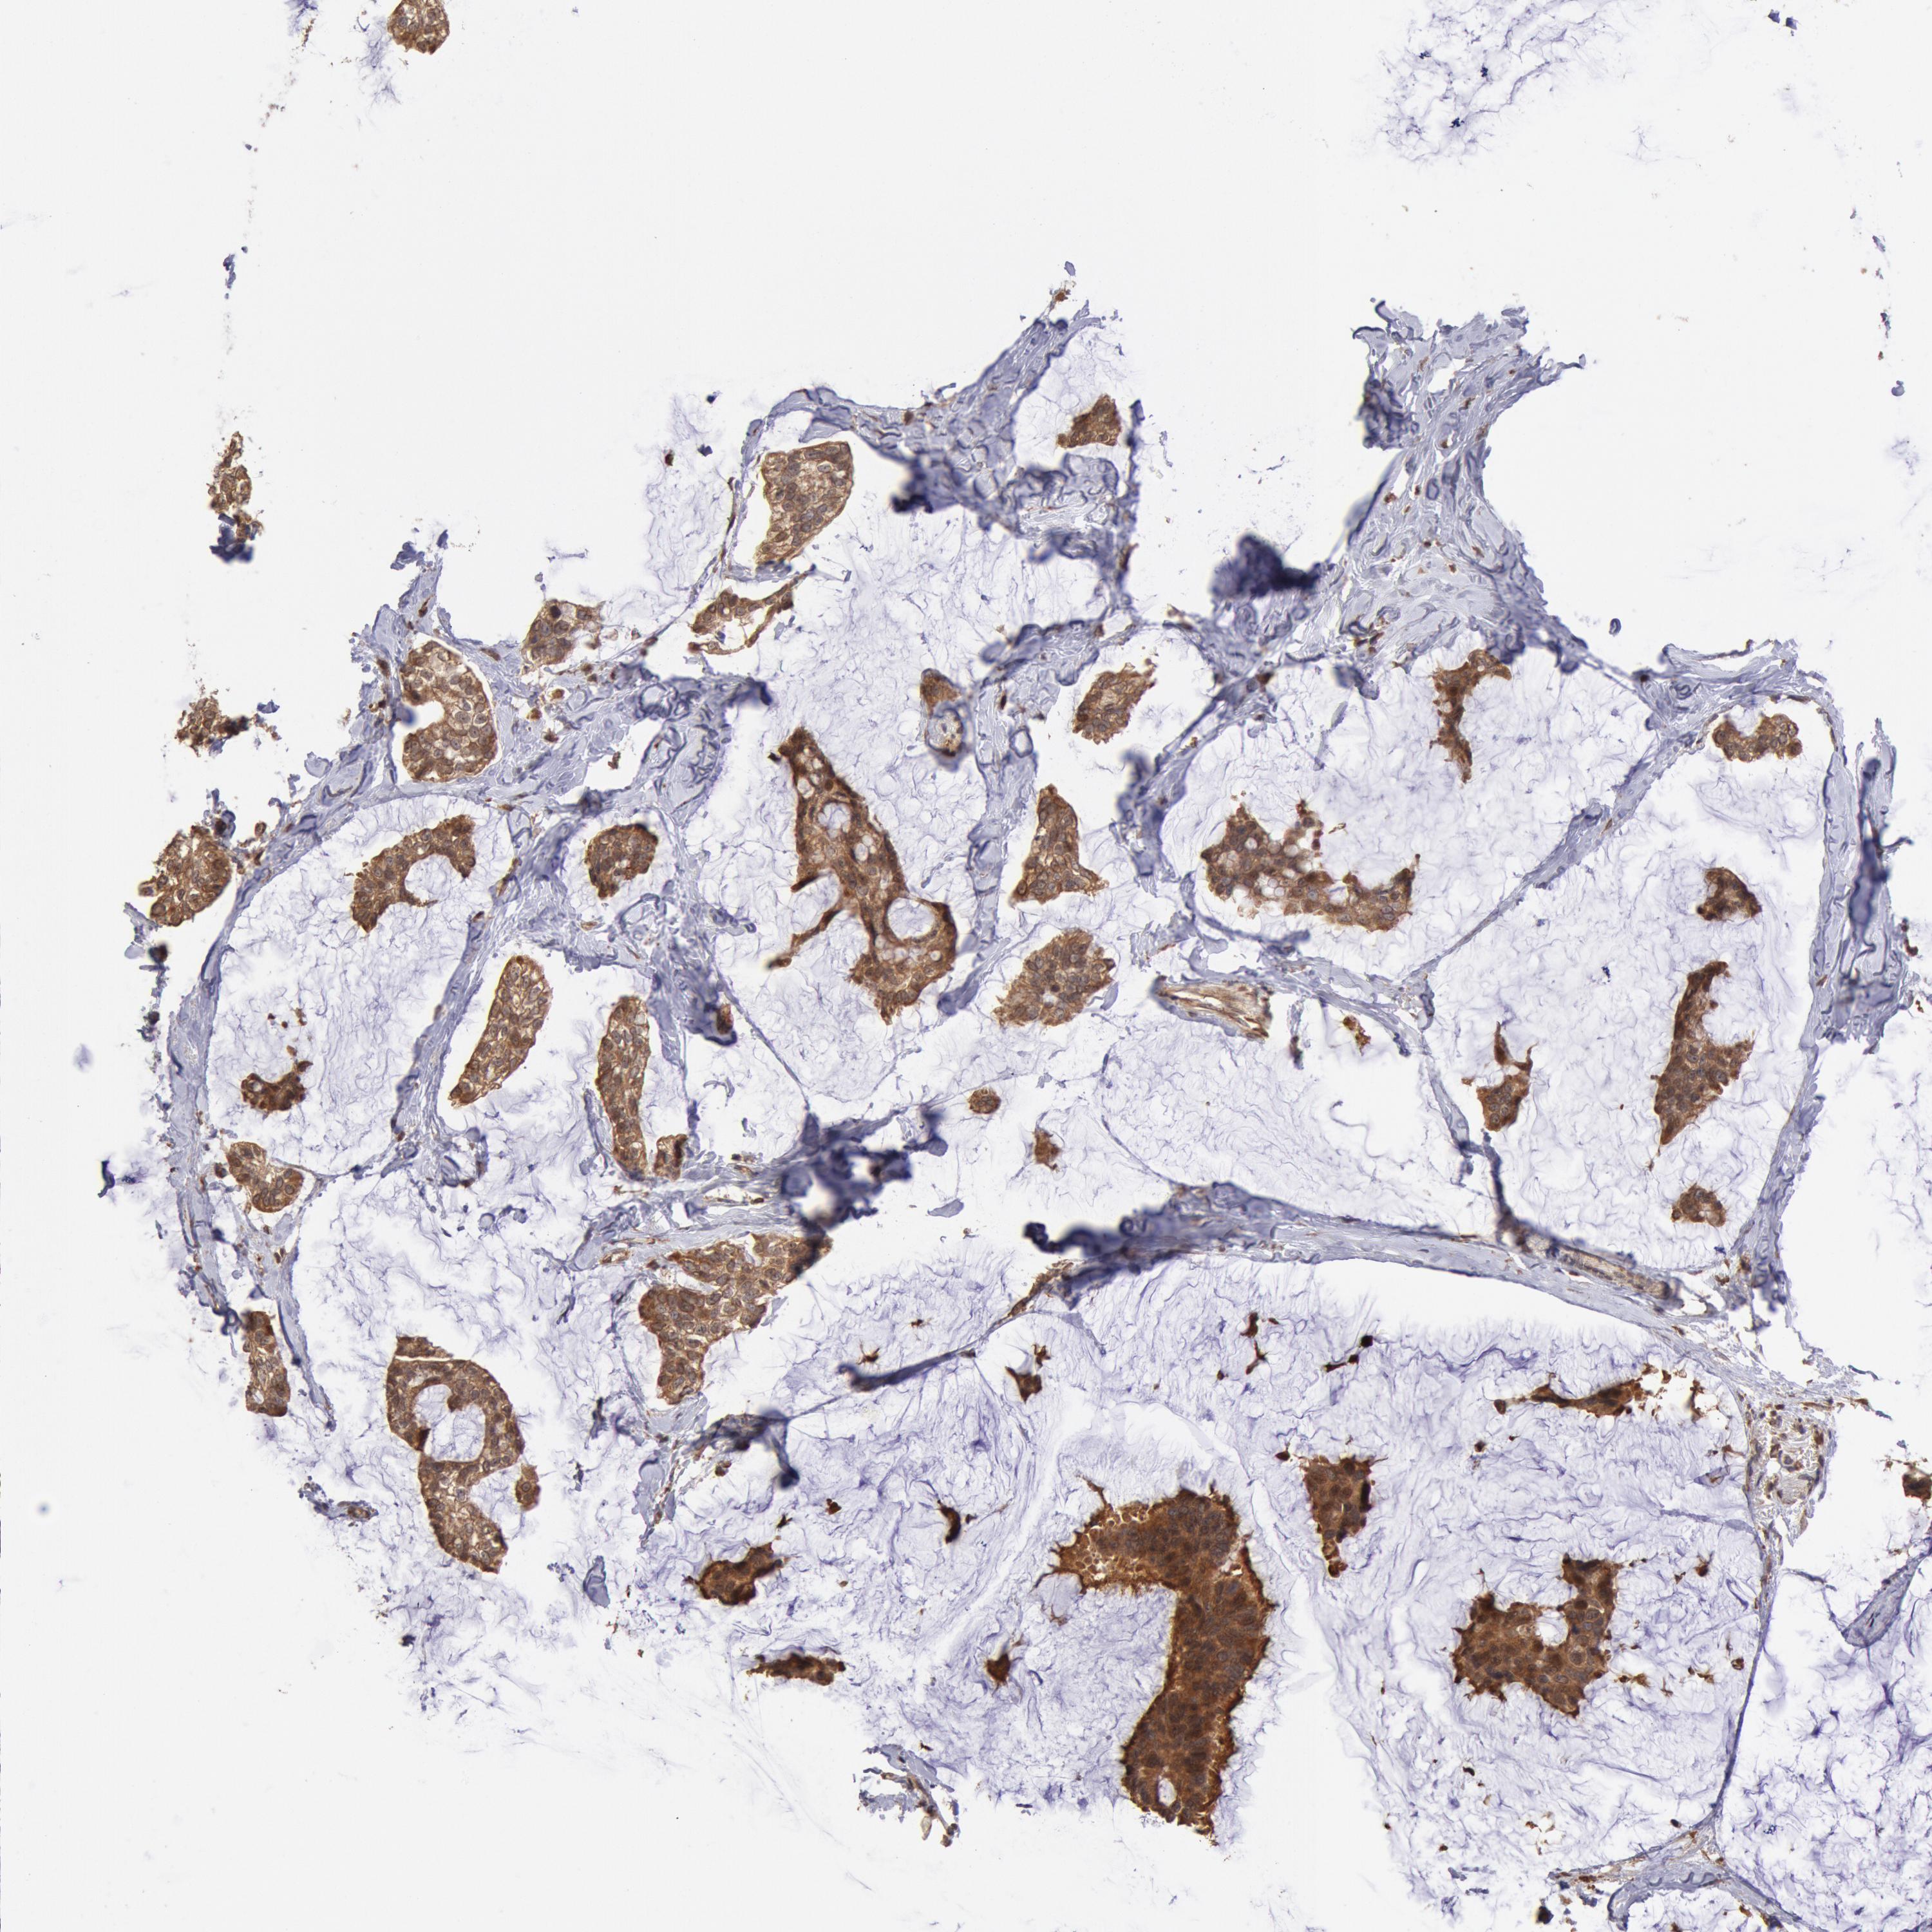

CANCER BREAST CANCER Show tissue menu

BRCA TCGA BRCA VALIDATION PROTEIN EXPRESSION

ANTIBODIES

AND

VALIDATION